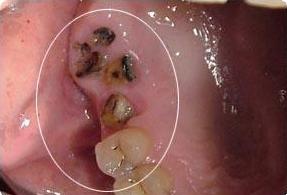

首先科普一下什么是残根。我们把一颗牙齿比作一颗"大树",牙科疾病好似"虫子",一直在不断攻击牙齿这颗"大树",最后只剩下树根。我们通常把这种残缺程度的牙齿称为残根。

对于残根的去留问题,主要是基于两方面的考虑。一方面是患牙是否有炎症,炎症是否可以通过控制和治疗来维护口腔健康;另一方面是患牙经过治疗后能否恢复功能,像残根过短不能利用也是要拔除的。

不管最终决定要不要残根,残根一定不要放任不管。残根使牙齿的髓腔、根管暴露于口腔充满细菌的环境中,进一步还可以引起全身的其它疾病。

牙根残缺会导致食物嵌塞,清洁不到位导致细菌感染,诱发牙龈炎、龋齿等一系列牙科疾病。最严重的情况牙齿出现松动,一旦咀嚼硬物容易崩牙或脱落。

残根会不定期刺激摩擦损伤口腔内的粘膜,会让娇嫩的口腔粘膜吃不消,容易形成创伤性溃疡。同时也大大提高了患癌风险,易引发舌癌、口腔癌等后果。